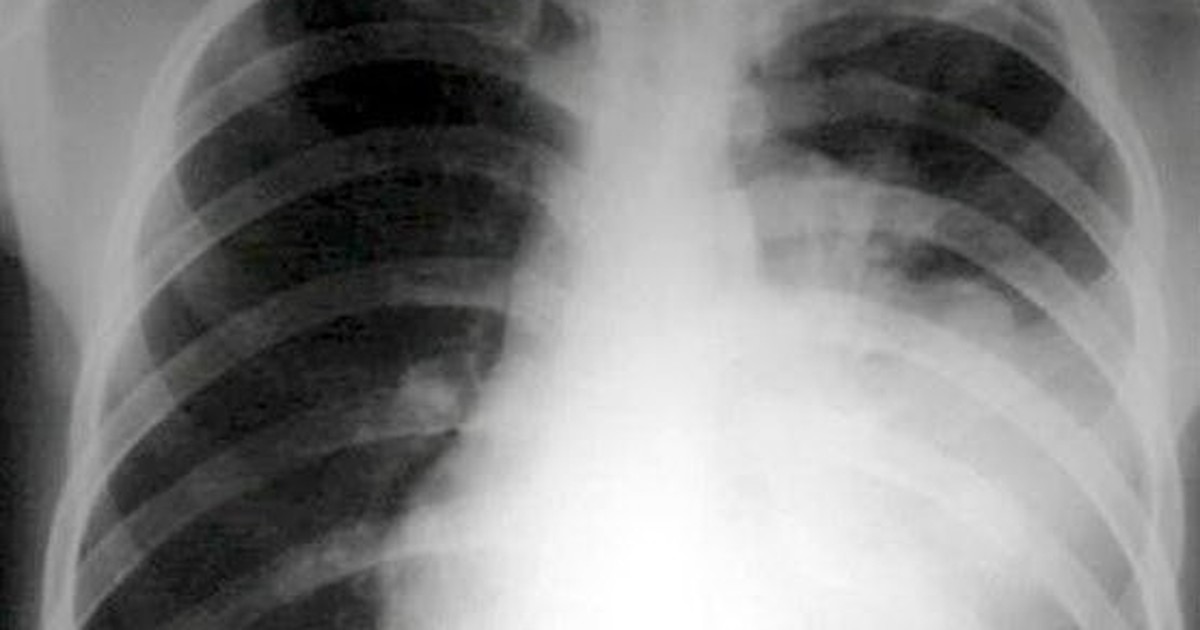

Coi chừng nhầm tưởng ung thư phổi với bệnh hô hấp

Bởi đặc tính như nói trên, nên bệnh nhân mắc ung thư phổi thường được